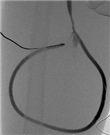

患者1 男性,63岁。因右颈内带隧道带涤纶套(tunnel-cuffed catheter,TCC)血透导管感染2个多月于2019年7月31日入院。血透通路史:患者2015年10月起因糖尿病肾病大量蛋白尿、低蛋白血症,出现全身浮肿,内科药物治疗效果不佳,遂行右颈内无隧道和涤纶套透析导管(non-cuffed catheter,NCC)临时血透4次后拔除导管。2015年12月再次出现全身浮肿,行右股NCC。至2016年1月拔除右股NCC,行右颈内TCC。2019年5月右颈内TCC感染,出现导管相关性菌血症,外院予全身性抗感染治疗及抗生素封管2周。入院后行四肢静脉造影示上腔静脉闭塞,奇静脉开放,导管尖端位于上腔静脉奇静脉开口处。下肢中心静脉通畅。患者双上肢无合适浅静脉行自体动静脉内瘘。在外周及导管血培养阴性的前提下于2019年8月8日神经阻滞麻醉下行右下肢股浅动脉-股浅静脉即穿型AVG成形术(6 mm×500 mm,Flixene,美国Atrium公司)。术后24.5 h使用17G针穿刺人工血管透析,止血时间8 min,穿刺点无渗血。并于2019年8月12日拔除右颈内TCC,2019年8月22日出院。无围术期感染、伤口延迟愈合,无单神经病变及动脉缺血发生。术后随访1年,术后8个月造影显示静脉吻合口稍狭窄,穿刺点无狭窄(图1)。

Flixene™是国内上市的第二款即穿型人工血管,该款人工血管的管壁结构与Acuseal™不同,其三层均由ePTFE材料构成,只是中间层密度更高,达到减少穿刺后渗血的要求。因此该款人工血管不存在管壁分层的问题。在我们的实际应用中,均可术后早期穿刺使用,无针眼渗血、皮下血肿发生,护理操作同普通人工血管,容易穿刺。管壁较Acuseal™柔软、薄,容易缝合,与缝合传统人工血管差别不大。图2显示病例2皮下隧道非常表浅,但该病例皮肤愈合良好,未出现皮肤坏死。病例1已随访1年,术后8个月造影显示穿刺点无狭窄,仅常见的静脉吻合口狭窄,无感染、窃血、假性动脉瘤等其他并发症。文献报道显示Flixene™和传统人工血管通畅率相仿。Sutaria 和Gilbert[9]报道的141例植入Flixene病例的1年初级通畅率、初级辅助通畅率、次级通畅率分别为48.7%、56.6%、83.6%。Hinojosa等[10]报道了24例植入Flixene病例,12个月的初级通畅率为41%。相关Meta分析报道,Flixene人工血管术后12个月初级通畅率为43.3%(95%CI:31.6~55.4),次级通畅率为73.4%(95%CI:63~82.7)[11]。另外,感染发生率也不劣于传统人工血管。Sutaria 和Gilbert[9]报道的141例建立Flixene即穿型人工血管患者中,8例(5.7%)发生了移植物感染。我们的初步临床应用显示Flixene™是又一款安全、有效的即穿型人工血管,某些特性还优于Acuseal™。在手术操作中,Flixene产品自带Slider移植体放置系统,人工血管一端具有与隧道器预链接的接头。其隧道器通过性能好,弯度合适,但不适用于其他6 mm直径人工血管产品。Flixene™人工血管由柔软、透明的聚乙烯保护性操作封膜保护,待人工血管全部埋于隧道后才取出保护性封膜。可减少置入时牵拉对组织的损伤和对人工血管本身的损伤,从而降低术后水肿、感染的并发症;还可有效防止置入过程中人工血管的污染可能,从而降低手术相关感染风险。术中需注意:(1)确保预链接接头、保护性封膜完整拿出;(2)在剪切保护套时,切勿剪切人工血管壁的任何部分。